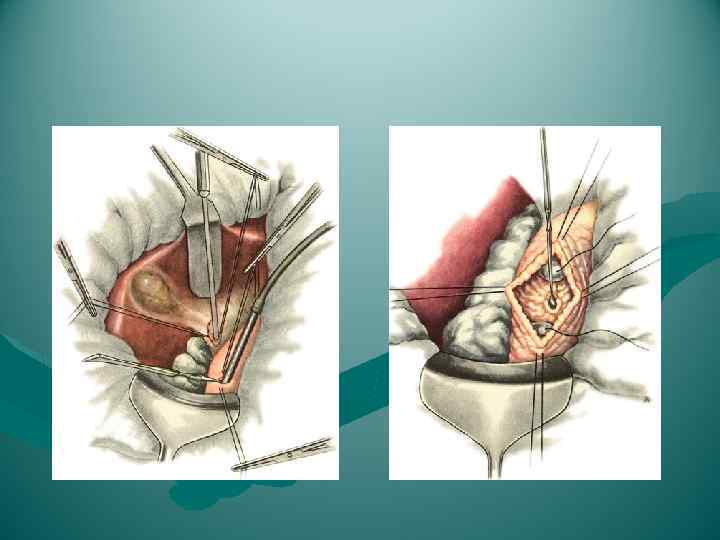

ВИДЫ ОПЕРАЦИЙ НА ЖЕЛЧНЫХ ПУТЯХ 1. Холецистотомия 2. Холецистостомия 3. Холецистэктомия - от дна (антеградная) преимущество • надежная идентификация отдельных элементов шейки пузыря недостаток • большая кровоточивость - от шейки (ретроградная) преимущество • малая кровоточивость при выделении желчного пузыря (перевязка a. cystica); • предотвращается возможность проталкивания мелких камней из пузыря в ductus choledochus (перевязка d. cysticus) - комбинированный способ 4. Холецистоэнтеростомия 5. Холедохотомия - эксплоративная (во время холецистэктомии) - трансдуоденальная 6. Холедоходуоденостомия 7. Папиллосфинктеротомия

ВИДЫ ОПЕРАЦИЙ НА ЖЕЛЧНЫХ ПУТЯХ 1. Холецистотомия 2. Холецистостомия 3. Холецистэктомия - от дна (антеградная) преимущество • надежная идентификация отдельных элементов шейки пузыря недостаток • большая кровоточивость - от шейки (ретроградная) преимущество • малая кровоточивость при выделении желчного пузыря (перевязка a. cystica); • предотвращается возможность проталкивания мелких камней из пузыря в ductus choledochus (перевязка d. cysticus) - комбинированный способ 4. Холецистоэнтеростомия 5. Холедохотомия - эксплоративная (во время холецистэктомии) - трансдуоденальная 6. Холедоходуоденостомия 7. Папиллосфинктеротомия